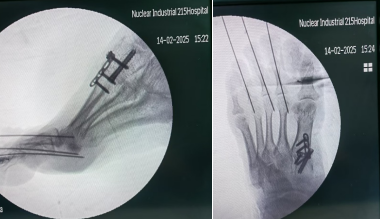

术中情况